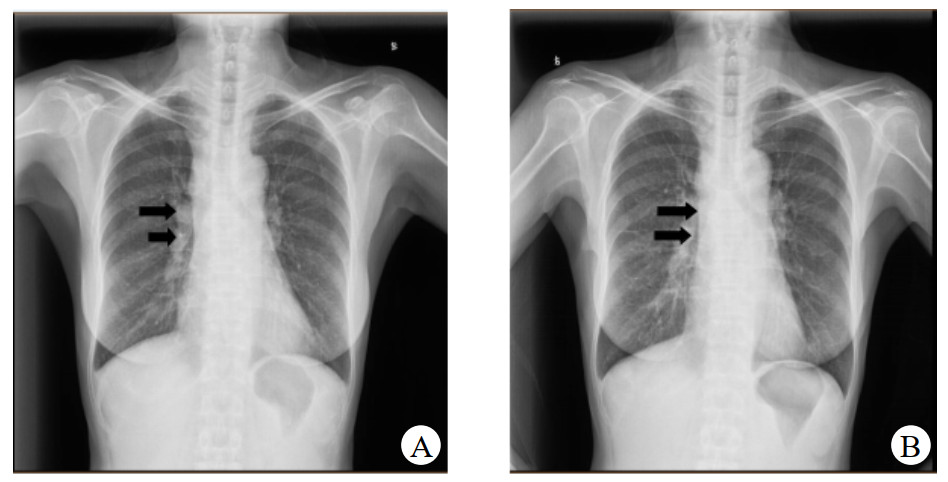

患者于2019-06-17因发热及头痛等不适来本院诊治。查体:体温38.5℃, 心率96次/min,呼吸20次/min,血压132/92 mmHg(1 mmHg=0.133 kPa)。结合症状及既往就诊经历,诊断考虑:发热查因;肺门淋巴结肿大。鉴别诊断:肺结核、淋巴瘤、结节病。同时患者外周血白细胞(WBC)及降钙素原(PCT)升高,不排除细菌感染, 予莫西沙星400 mg治疗5 d, 并在应用抗生素前留取病原学标本。期间行经气管镜超声引导针吸活检术(endobronchial ultrasound-guided transbronchial needlle aspiration, EBUS-TBNA),但无阳性结果。入院后所行的PET-CT提示肿大淋巴结考虑淋巴瘤。双肺小结节,考虑炎性肉芽肿。骨穿无异常结果, 以“肉芽肿(纵膈淋巴结)”为主要诊断出院。图 1为入院后两次胸部平片影像检查结果,可见右肺门影增浓。

| A:2019-07-15检查;B:2019-08-27检查 图 1 CT检查示右肺门影改变 |